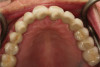

Fig 12. Frontal view (Fig 12) and occlusal view (Fig 13) of clinical application of dual-axis principles. (Images courtesy of Costa Nicolopoulos, BDS)

Figure 12

Fig 13. Frontal view (Fig 12) and occlusal view (Fig 13) of clinical application of dual-axis principles. (Images courtesy of Costa Nicolopoulos, BDS)

Figure 13